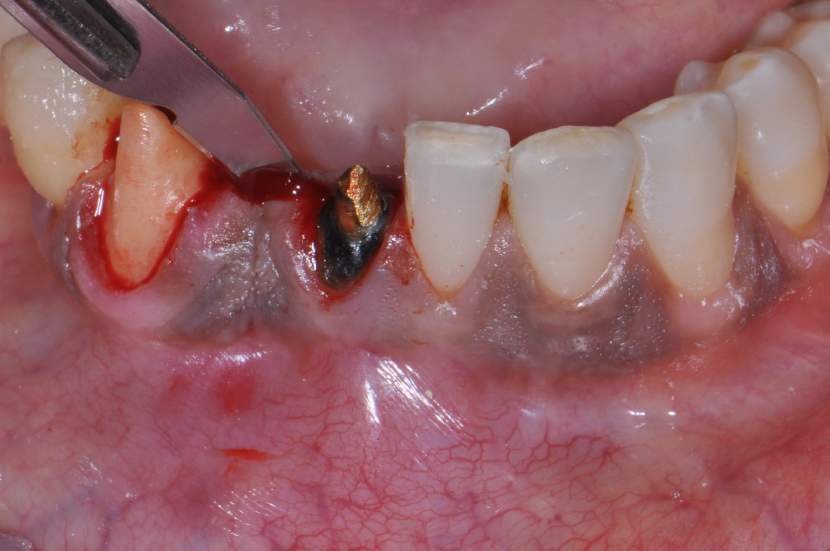

CASO CLÍNICO

Paciente com perda do incisivo central inferior do lado direito, utilizando uma prótese fixa em zircônia com estética e adaptação deficientes.

TÉCNICA CIRÚRGICA

O procedimento cirúrgico para os implantes Slim segue um protocolo semelhante como outros implantes, porém muito simplificado. Normalmente utilizase a técnica anestésica infiltrativa. Um retalho mucoperiosteal deve ser rebatido para uma observação direta do rebordo ósseo disponível. No entanto, quando o tecido queratinizado e o volume ósseo abundantes estiverem presentes, uma cirurgia flapless é muitas vezes o protocolo cirúrgico de escolha.2